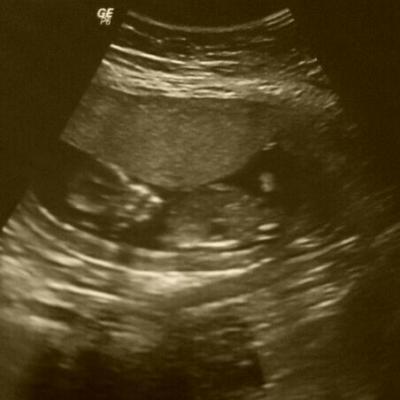

Bericht vom FA-Termin heute, der alles in allem 1 Stunde gedauert hat: Herztönchen von aussen zum 1. Mal bestens gehört. Ein unbeschreiblich erleichterndes Gefühl! Danach lange US gemacht. Köpfchen SSW 14+4 und SSL mit 6,9cm genau richtig bei 13+1 Nackenfalte < 1.75 Grosse Blutentnahme, Mutterpass wurde heute angelegt bleibt aber bei FA. Alles soweit gut und zeitgerecht. Uffff jetzt kann ich es hoffentlich ohne Panik und Ängste angehen.

Bild zu Zurück vom FA - Forum für April - Mamis